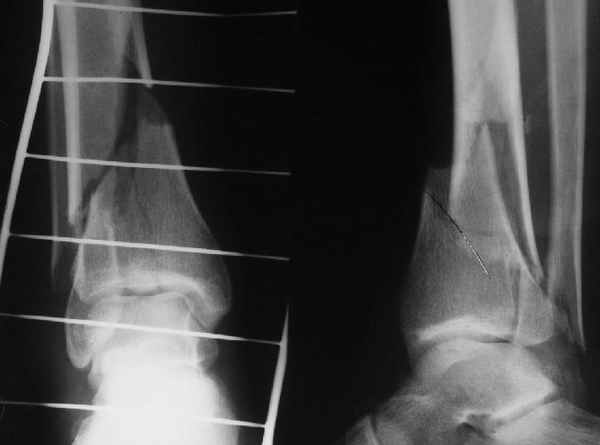

Отправитель: А.Миронов 13 Апрель 2005, 16:53

При штифтовании ортопедическим столом не пользуйтесь?

Кликните для загрузки файла 1.JPG